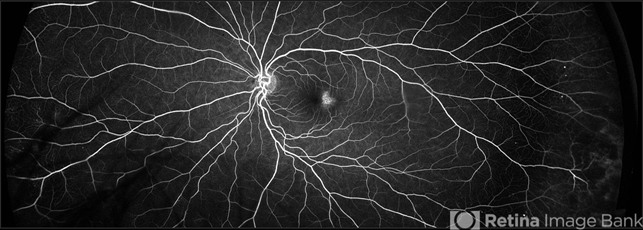

- Fluorescein angiography of the left eye of a 45-year-old African American female with MacTel type 2 and Type 2 Diabetes. This angiogram demonstrates peripheral microaneurysms characteristic of mild non proliferative diabetic retinopathy and temporal foveal leakage with telangiectatic macular capillaries classic for MacTel type 2. There is a well-established association between the two conditions.